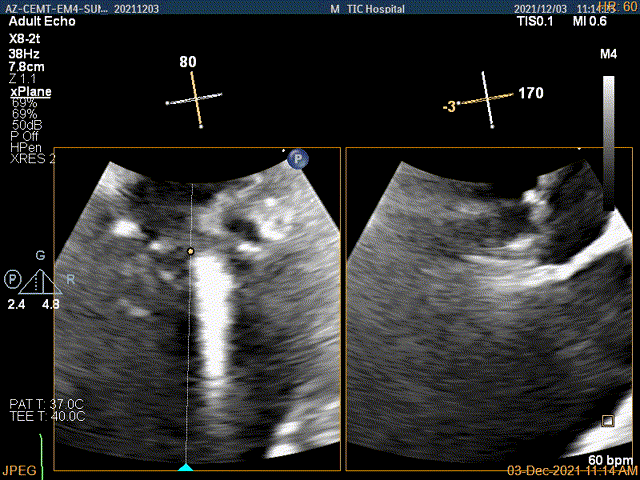

3D视图菲薄的卵圆窝,穿刺点位近似于3点位

3D视图下大鞘位置及长度测量

2D视图下trajectory

4Ch验证前后叶抓捕后有典型的bouncing征

x-plane平面测量确认后叶抓捕长度大于6mm